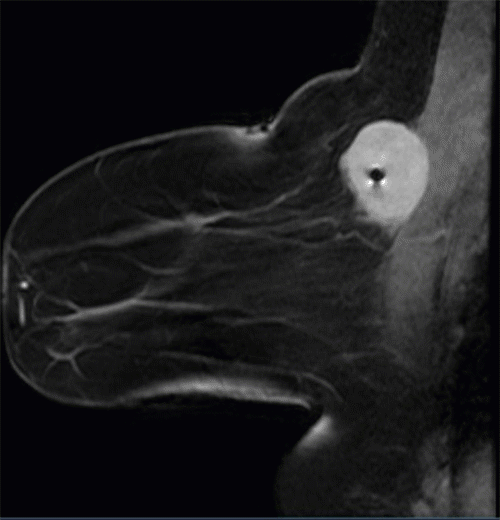

The core needle biopsy slides from the outside facility were submitted for second and third opinions to our institution's pathology department and Memorial Sloan Kettering, which confirmed metastatic sarcoma. She then underwent a bilateral breast magnetic resonance imaging (MRI) (Figure 1) as well as a whole-body positron emission tomography (PET) scan. PET scan showed mild uptake (1.5 standard uptake value [SUV]) of a 9 mm nodule in the right lower lobe of the lung (Figure 2) as well as in the right breast mass. After a multidisciplinary tumor board discussion, it was decided that surgical excision of the breast mass with a sentinel lymph node biopsy would precede chemotherapy. While there is little evidence for lymph node metastasis in liposarcoma, a sentinel node biopsy was performed for a more thorough approach to the breast lesion. The medical oncology team agreed this would be an appropriate course, given that her sub-centimeter pulmonary nodule did not necessarily mandate systemic treatment in the neoadjuvant setting. Moreover, the patient herself was very motivated to have her mass removed as it was causing her pain and discomfort.

Figure 1. Bilateral breast MRI with intravenous (IV) contrast Axial T2 STIR sequence. Published with Permission

Image depicts right breast mass with intimal connection with pectoralis muscle, 3 x 3.5 x 4.5 cm, very dense lobulated mass with postbiopsy clip marker

Figure 2. Bilateral breast MRI with intravenous (IV) contrast Sagittal T2 STIR sequence. Published with Permission

Image depicts right breast mass with intimal connection with pectoralis muscle, 3.0 × 3.5 × 4.5 cm, very dense lobulated mass with postbiopsy clip marker